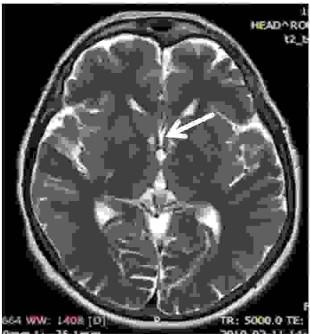

Parzysta struktura zaznaczona strzałką na skanie T2 rezonansu magnetycznego to: